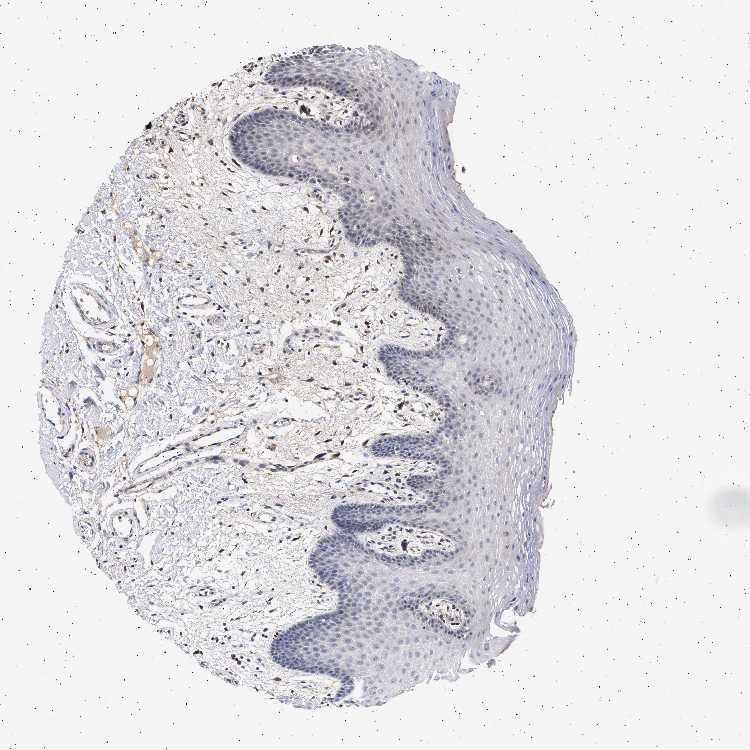

TISSUE PRIMARY DATA ORAL MUCOSA Show tissue menu

ORAL MUCOSA - Antibody stainingi

Antibody staining in the annotated cell types in the current human tissue is reported as not detected, low, medium, or high, based on conventional immunohistochemistry profiling in selected tissues. This score is based on the combination of the staining intensity and fraction of stained cells.

Each image is clickable and will lead to virtual microscopy that enables deeper exploration of all samples and also displays staining intensity scores, fraction scores and subcellular localization as well as patient and tissue information for each sample.

Antibody HPA021237Antibody HPA050448

Squamous epithelial cells Not detectedHigh